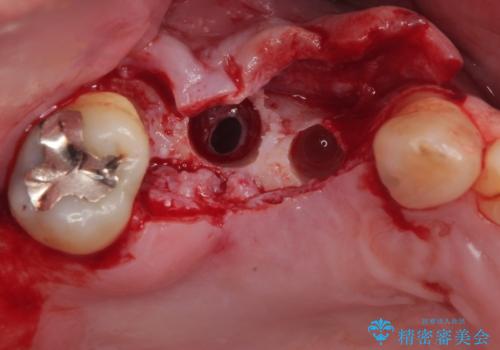

上顎は左右ともに骨が少ない状態であり、特殊なドリルを用いた歯槽骨の拡大や自家骨挙上などを行いながらインプラントを埋入していくこととしました。

- 外科手術のため、術後に痛みや腫れ、違和感を伴います